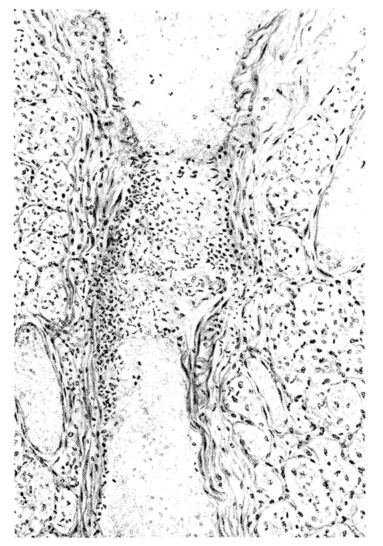

FIG. I. AUTOPSY NO. 99. ACUTE HEMORRHAGIC AND ULCERATIVE LARYNGOTRACHEITIS.

FIG. I. AUTOPSY NO. 99. ACUTE HEMORRHAGIC AND ULCERATIVE LARYNGOTRACHEITIS.

Early in the disease the congestion and the hemorrhages that have been described in the mucous membrane of the nasopharynx (14 and 94) are also conspicuous features in the lining of the trachea and bronchi (Fig. I). This membrane is swollen, turgid, red, and covered by a copious, mucous exudate which may be clear, but much more frequently is blood-stained or opaque and yellowish in color. The blood, variable in amount, may be fresh and red; and after the mucous exudate on the surface is removed, more intense red foci stand out on the congested base (47, 90, 157). Frequently, as the bronchi are approached, the red color of the mucosa becomes more intense and may have a garnet tinge. Membranes such as are encountered in the more usual necrotizing inflammatory processes, like diphtheria, have not occurred in the trachea and larger bronchi in this series (108, 128, 157).[3] The exudate peels off readily, and as indicated above, leaves a velvety red surface, 14dotted here and there with darker or more intensely red foci. Small ulcerations of the mucosa occur, but are inconspicuous (82, 156). As the finer ramifications of the bronchi are approached, the accumulation of the exudate in their lumina becomes more and more marked, and on cross section of the lung, they often stand out conspicuously on account of their increased size and projecting, seromucous, blood-stained content (101, 149, 162).